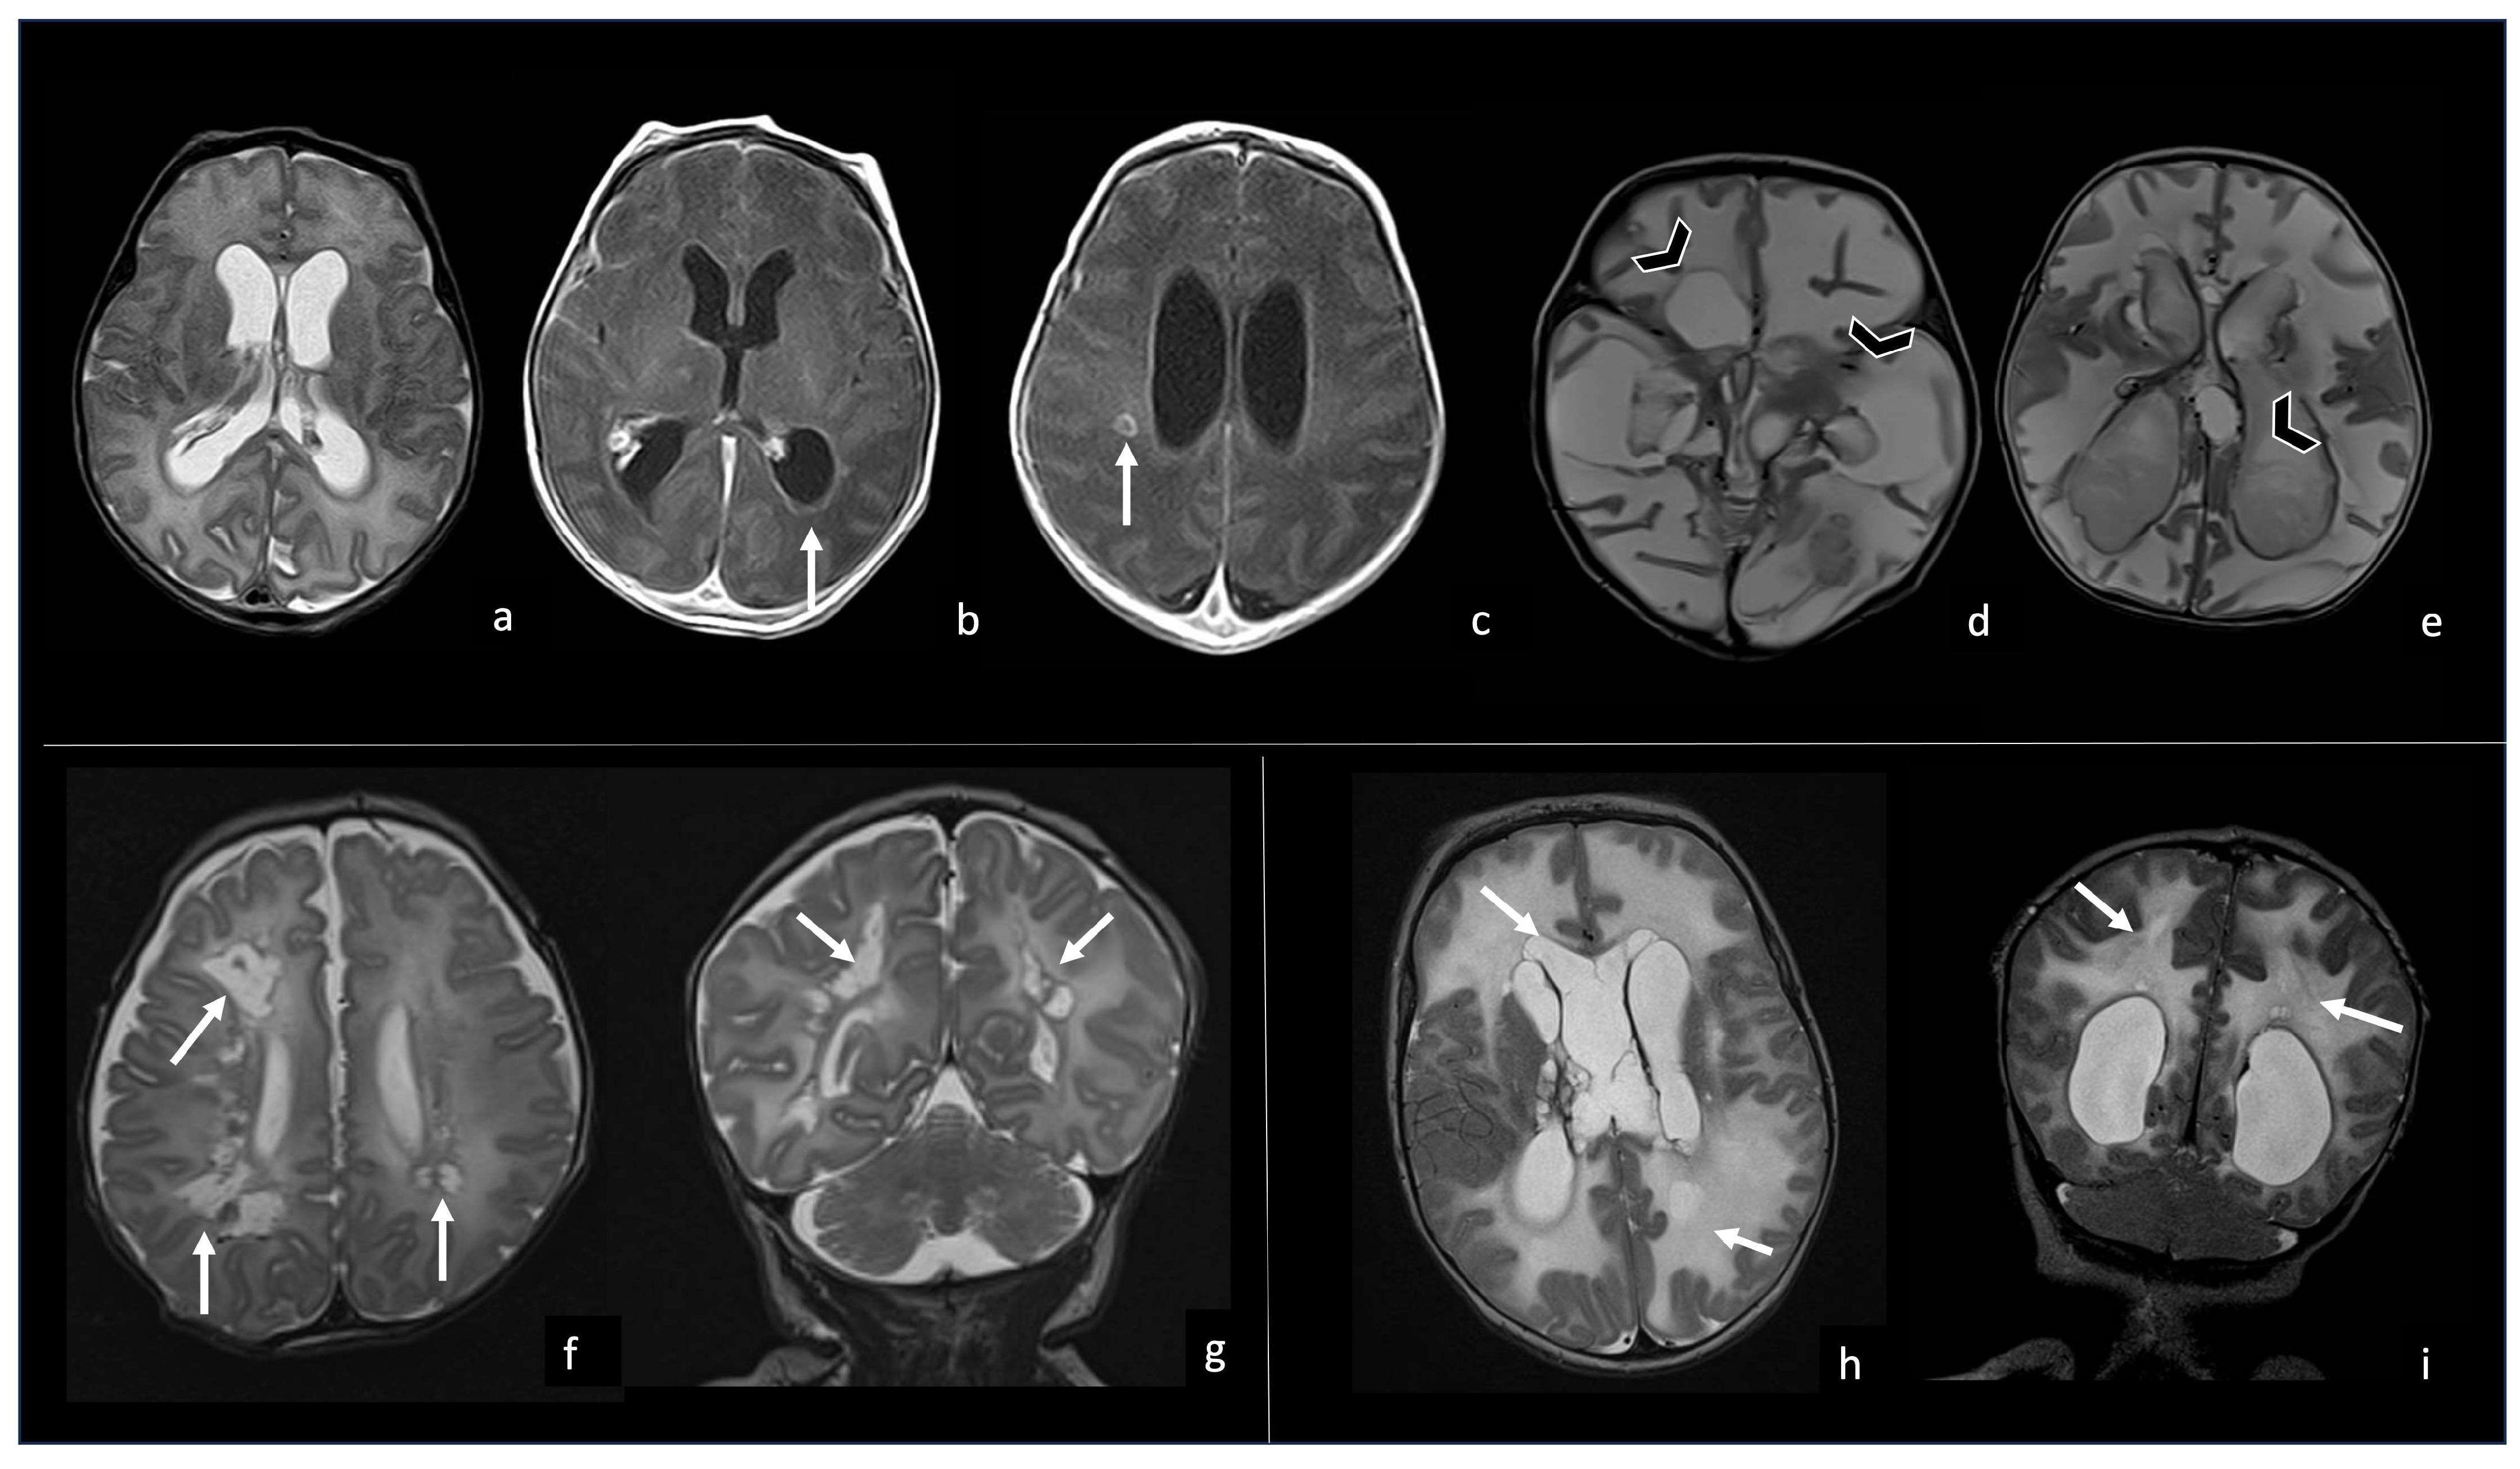

5.1. Choroid Plexitis and Ventriculitis

5.3. Ventriculomegaly and Hydrocephalus

5.4. Effusions and Empyema

6. Meningoencephalitis Stage: Neuroradiological Findings

6.2. Infarcts